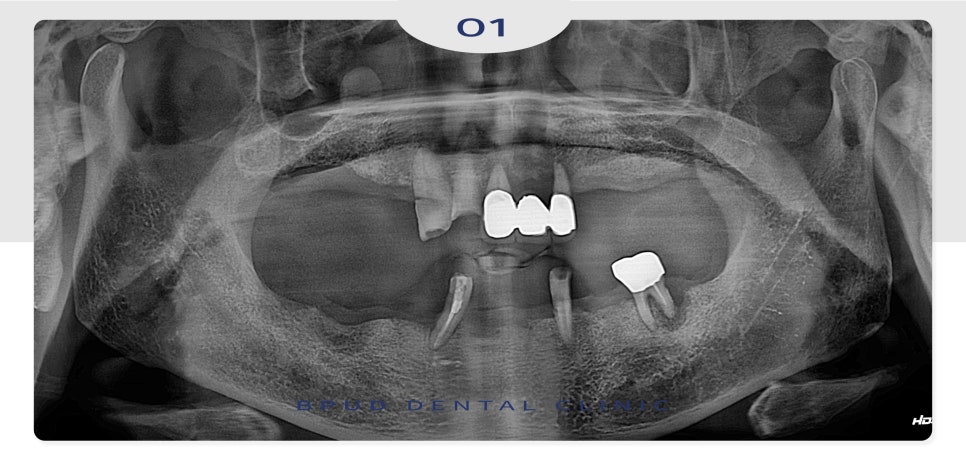

오늘은 남아 있는 치아가 거의 없어

위, 아래 전악 임플란트를 진행하신

환자분을 소개해 드리도록 하겠습니다.

구강 내 치아가 거의 없어

식사도 잘 못하셔서 불편하시며

심미적으로 자존감도 많이 떨어져

있는 상태였는데요.

남아 있는 치아들도 예후가 좋지 않아

모두 발치한 후 부평역치과 전체임플란트를

진행하시기로 계획을 수립하였습니다.